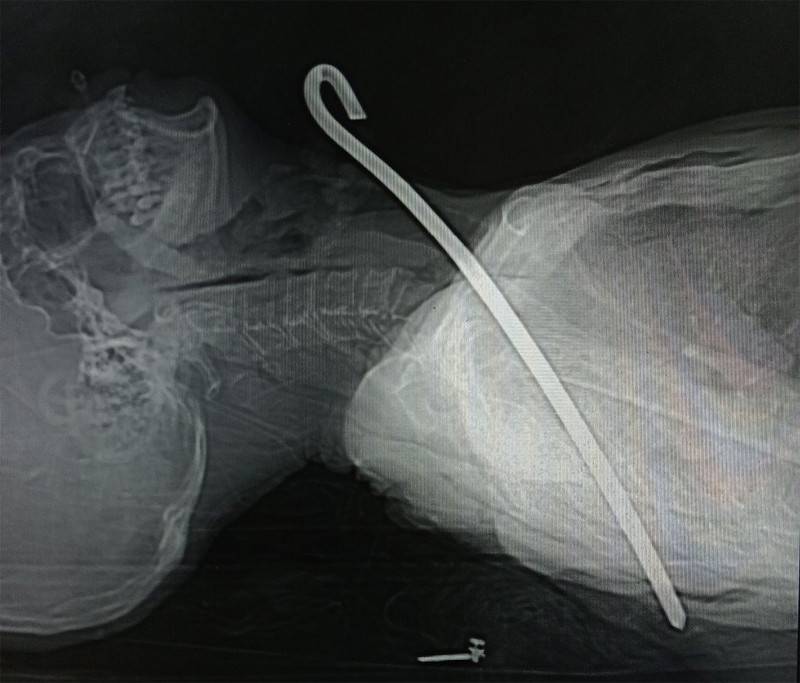

Ông Đ. bị vấp ngã, trúng vào thanh sắt. Ông được người nhà đưa vào bệnh viện cấp cứu trong tình trạng bị thanh sắt dài 30cm xuyên từ vùng cổ qua phổi phải và trung thất xuống vùng ngực bên trái.